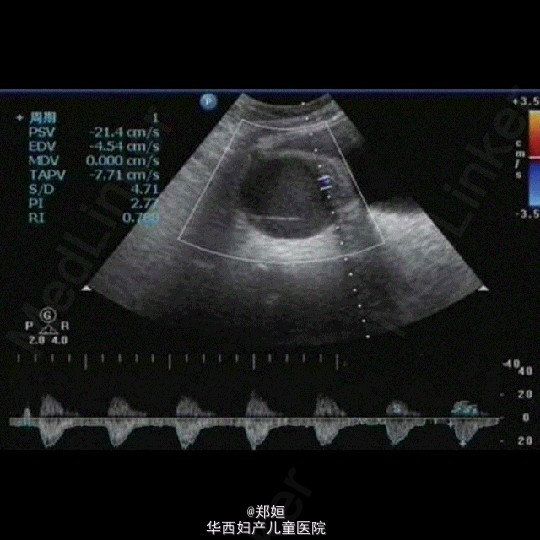

子宫腺肌症双侧卵巢囊肿超声表现

子宫腺肌症

卵巢囊肿

女,34岁,6年前体检发现右附件包块

子宫腺肌症双侧卵巢囊肿